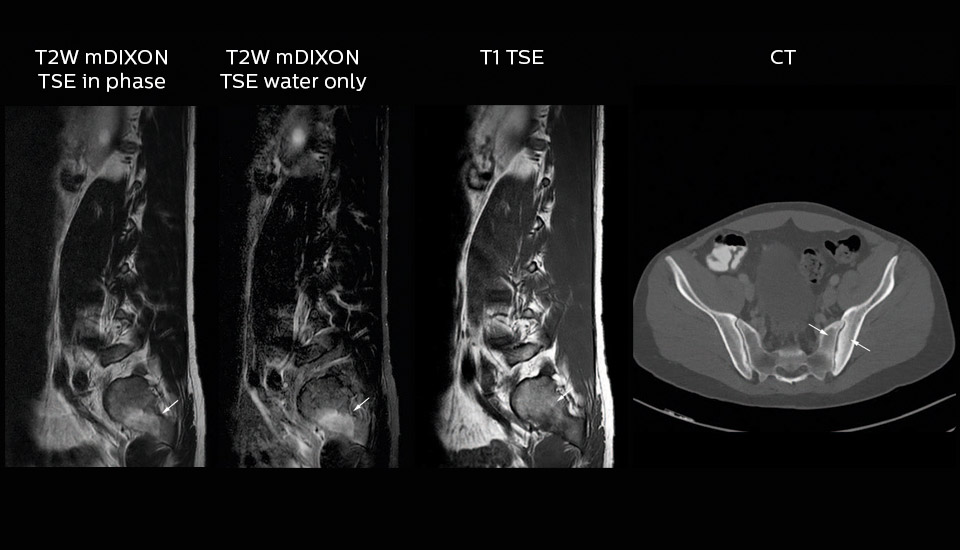

“In our lumbar spine MRI, the value of mDIXON TSE is so obvious. Normally we perform T1 and T2 scans in sagittal and transverse orientation.It used to take too much time to add a sagittal T2 with good fat suppression.But now, using mDIXON TSE, we get the sagittal T2 fat suppressed images ‘for free’, that is: without adding time.”

“Diagnostically that is a great benefit. I sometimes see abnormalities in the fat suppressed sagittal T2 that would be quite challenging to notice in the T2 without fat suppression. There have been several diagnoses that I could make easier because of our exam setup with mDIXON TSE, such as sacrum insufficiency fractures and sacroileitis; these were more challenging with our previous exam setup.”